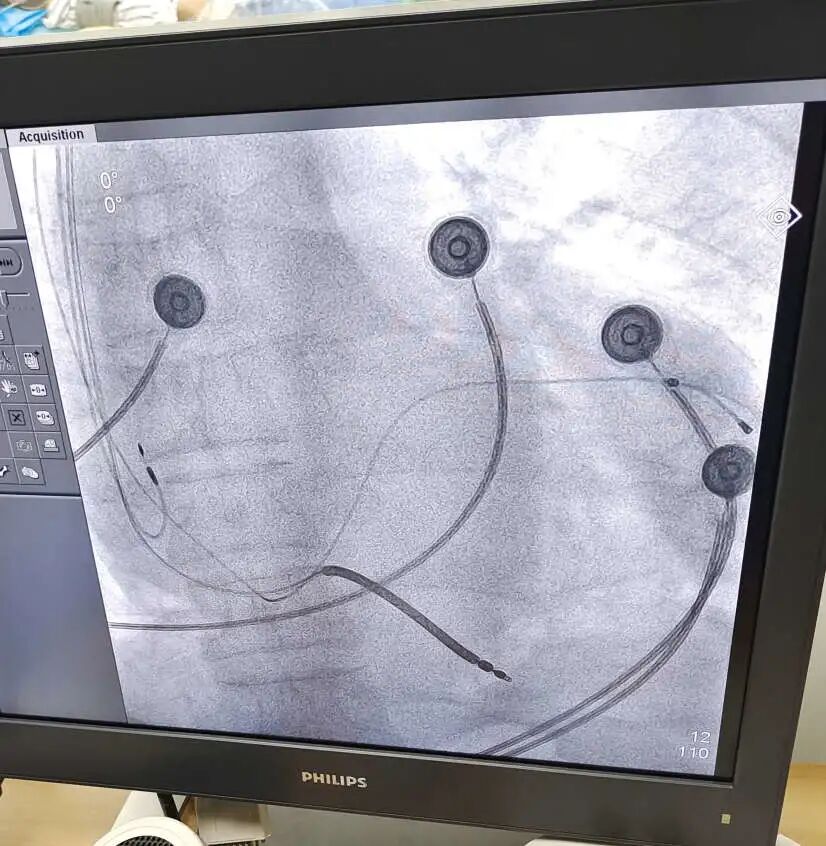

医 术 2021年9月6日 成都东篱医院 心内科李其勇主任带领科室团队 为一位患“扩张型心肌病 ”七十岁爷爷 成功施行“ CRTD植入术” 希望可以治好自己的“心病” 夏爷爷,70岁,十余年前就因活动后心累气促、活动耐受力下降,被当地医院诊断为“心力衰竭”,给予药物治疗后好转。近些年反复发作,后被诊断为“扩张型心肌病 全心增大 EF下降型心衰”,辗转于多家医院,治疗效果微乎其微。1个月前夏爷爷感到病情进一步加重,甚至走几分钟的路都得停一停、缓一缓,身体乏力,精神萎靡,夜间还存在呼吸困难的情况,于8月27日收入我院心内科。 心脏彩色多普勒超声提示:LA55*73*62,LV76,RA59*42,IVS11,EF37%。 腔内电生理图提示:QRS波163.89ms 新技术带来新希望 术前科室医疗组经过反复分析病情与家属沟通后,决定为夏爷爷植入CRTD(心脏再同步化治疗及埋藏式心脏自动除颤器)。 CRT(心脏再同步化治疗起搏器)可以保证心脏的左右心腔重新恢复同步收缩,减少由于心脏扩大导致的瓣膜返流,达到改善心衰,逆转心脏扩大的作用。 ICD(埋藏式心脏自动除颤器)则可以自动识别室性心动过速、室性纤颤等恶性快速心律失常,及时给予电学终止治疗。 CRTD将以上两种功能合二为一,该技术集起搏、治疗恶性心律失常、改善心力衰竭于一体,使慢性心衰病人恢复双心室同步收缩、改善心功能、从而降低心律失常的发作,提高生活质量,降低心衰住院率和死亡率。 CRTD成功植入,老人平安 手术器械的选择,手术的每一个步骤,术中可能出现的危急情况等,科室都做了充分的准备。9月6日,在李其勇主任的指导下,心内科医护团队紧密协作,克服患者靶血管相对细小的困难,最终选择适宜位点,成功植入电极,手术非常顺利。 安置后的CRTD 术后经胸部CT证实患者电级安装到位,程控起搏器各项数据工作良好。切口周围皮肤无红肿、无明显活动性出血疼痛,患者自述症状较前期缓解。从此,夏爷爷的心脏有了一个“新管家”,心功能将逐渐恢复!